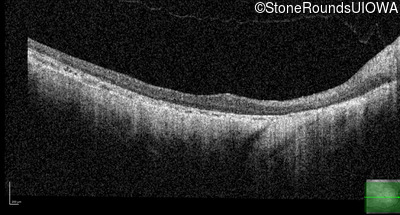

Optical Coherence Tomography - Right - 20/250 sc

Exemplar / OCT Stack